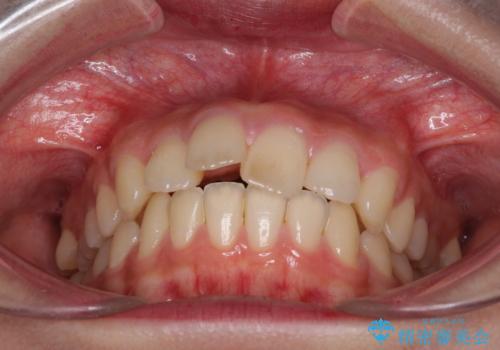

就職前にきれいな歯並びにしたい 大学生のインビザライン矯正

- 就職するまでに歯並びをきれいにしたいとのことで来院された患者様です。

前歯の叢生を気にしていましたが、極力突出感を改善できるようにすることとし、インビザラインにて矯正治療を行うこととしました。

改善の期待できない口元の突出感改善を希望されたため、いたずらに治療期間が延びましたが、きっちりと仕上がりました。